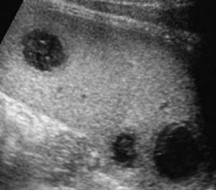

Identify this image.

Splenic granulomas